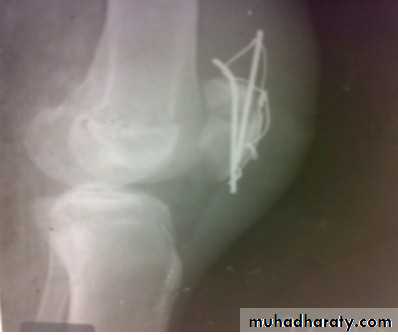

dynamic condylar screw and plate

Supracondylar fracture with its fixation by L – plate and screwsComplications